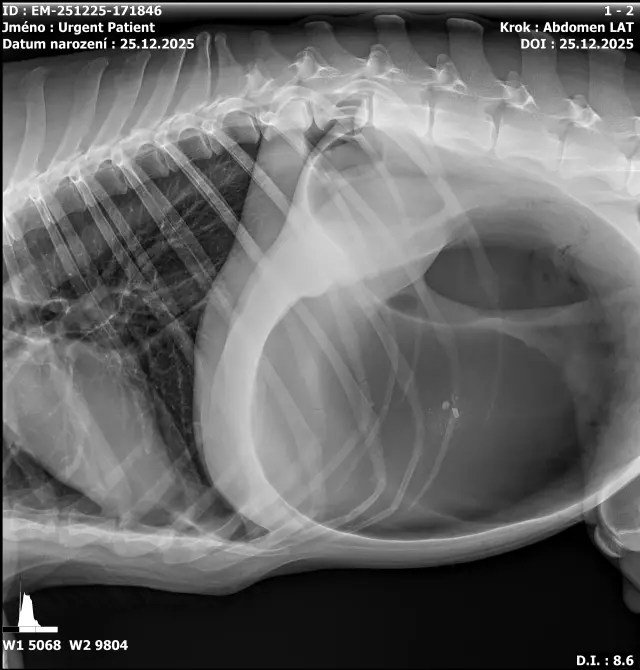

Fotogalerie